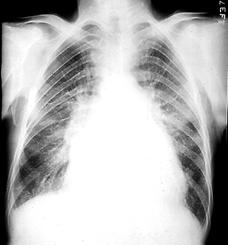

3. Rx. poate arata:

o silueta cardiaca mitrala,

largirea AS (PA, OAS, LS),

dublu contur dr.,

calcificari mitrale sau de AS,

VS mare sau mic,

semne de hipertensiune veno-capilara:

redistributie venoasa lobara sup,

edem interstitial,

linii Kerley exprima staza limfatica (A-la hil, B-la baza SM stransa, C-intre),

edem alveolar,

epansament pleural.

hemosideroza,

calcificari

pulmonare,

infarct pulmonar,

alte boli pulmonare

asociate.